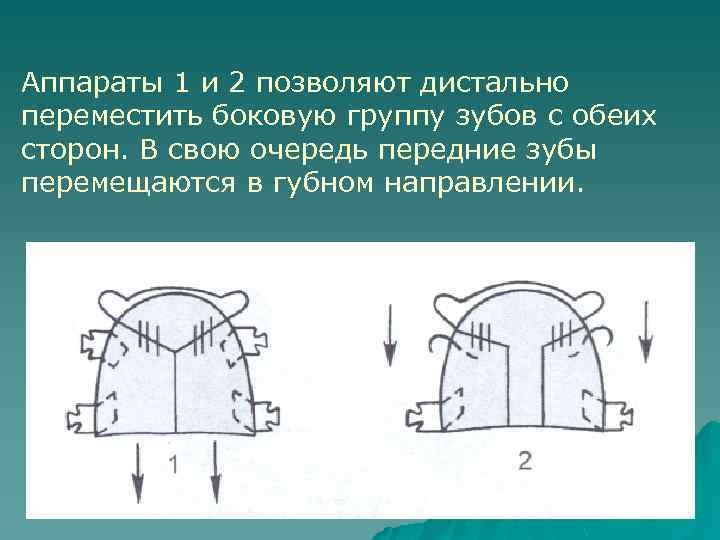

С целью создания места для клыка необходимо переместить боковые зубы дистально. Для этого можно использовать пластиночные аппараты

Аппараты 1 и 2 позволяют дистально переместить боковую группу зубов с обеих сторон. В свою очередь передние зубы перемещаются в губном направлении.